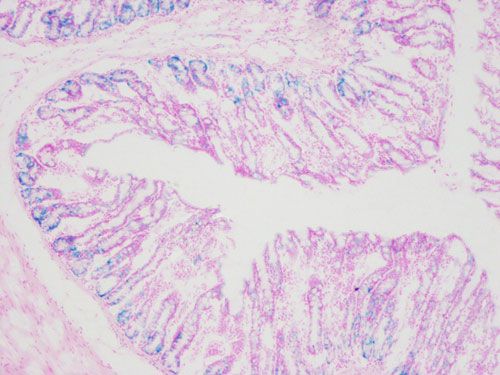

β-半乳糖甘酶染色,衰老細(xì)胞通常體積變會(huì)大,表達(dá)pH6.0時(shí)有高酶活性的β-半乳糖苷酶。染色中以X-ga1(5-溴-4-氯-3-吲哚-β-D-半乳糖苷)為底物,在衰老特異性的β-半乳糖苷酶催化下,半乳糖苷鍵被水解生成深藍(lán)色產(chǎn)物,光學(xué)顯微鏡下很容易觀察到變成藍(lán)色的表達(dá)β-半乳糖苷酶的細(xì)胞或組織。

實(shí)驗(yàn)結(jié)果展示:

β半乳糖甘酶染色-小鼠腸道

衰老細(xì)胞呈深藍(lán)色,細(xì)胞核紅色